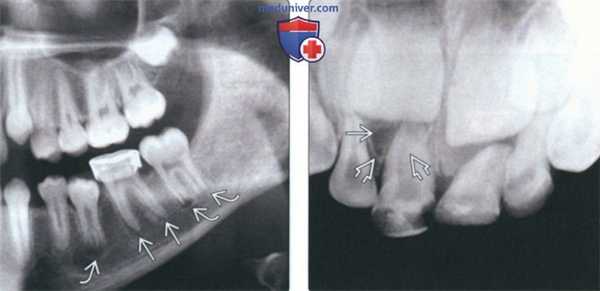

(Слева) На периапикальной рентгенограмме определяется склерозирующий остеит в области корней первого моляра нижней челюсти слева. Определяется также рарефицирующий остеит в области корней зуба. Обратите внимание на остеосклероз, «смешивающийся» с окружающей нормальной костью.

(Справа) На периапикальной рентгенограмме определяется хорошо отграниченное однородное затемнение с неровными краями у вершины первого моляра нижней челюсти справа. Пространства периодонтальной связки и твердые пластинки не изменены. (Слева) На периапикальных рентгенограммах нижних передних зубов определяется прогрессирующая периапикальная костная дисплазия. На рентгенограмме справа, выполненной через семь лет после левой, определяется постепенное нарастание минерализации очагов.

(Справа) На периапикальной рентгенограмме определяется луковицеобразное расширение кор ня с сохранением твердой пластинки и пространств ПДС, сопоставимое с гиперцементозом.

(Слева) На панорамной реформатированной КЛКТ определяется очаг смешанной плотности, образованный мелкими структурами, напоминающими зубы окруженный рентгенонегативным «ободком» и кортикальной пластинкой. Это составная одонтома - самая частая одонтогенная опухоль.

(Справа) На кадрированной панорамной рентгенограмме определяется однородный рентгеноконтрастный очаг, окруженный рентгенонегативным «ободком», связанный с мезиальным корнем второго временного моляра нижней челюсти справа и приводящий к его резорбции. Эта цементобластома смещает второй премоляр. (Слева) На окклюзионной рентгенограмме определяется экспансивный рентгеноконтрастный очаг однородной структуры с рентгенонегативным «ободком». Корни клыка и первого премоляра нижней челюсти слева изогнуты в язычную сторону в результате воздействия этой цементооссифицирующей фибромы.

(Справа) На кадрированной панорамной рентгенограмме визуализируется хорошо отграниченный очаг смешанной плотности, который был ошибочно принят за цементобластому, несмотря на наличие выраженной болевой симптоматики и отсутствие фиксации к корню зуба.